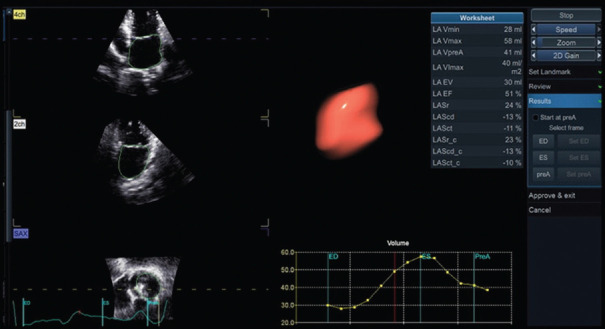

Abstract Image